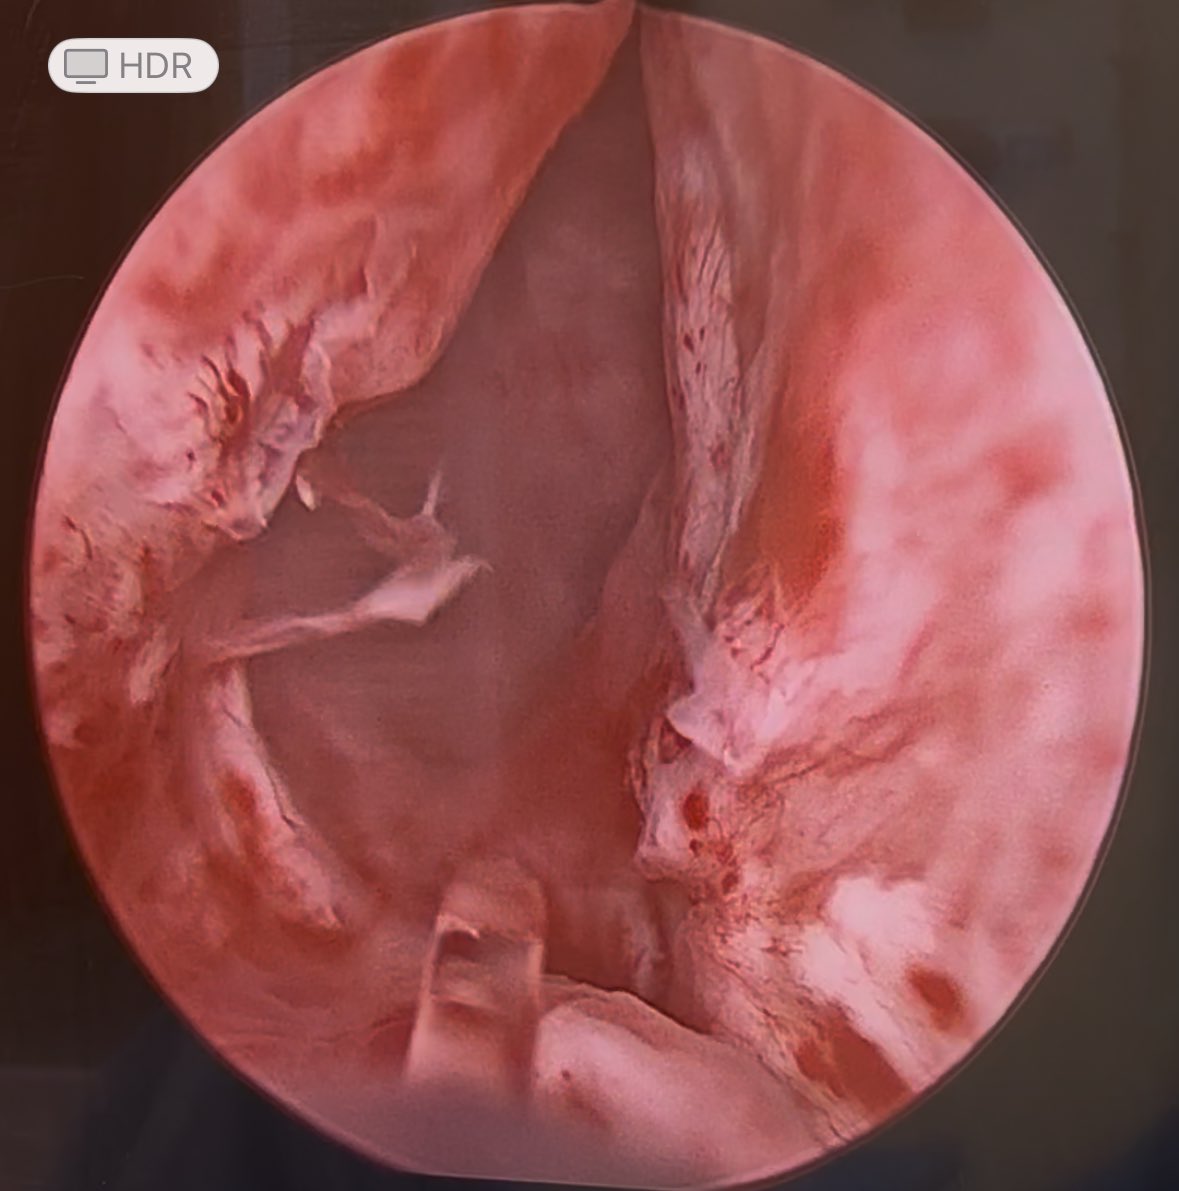

Over the last 36 months this individual underwent robotic waterjet therapy then 2 TURPs and resumed his BPH meds for persistent LUTs and hematuria. This week he underwent HoLEP to hopefully end the BPH journey. @NM_Urology @EndourologyNm